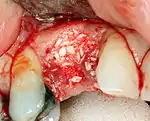

Hard tissue (bone) reconstruction

Bone grafting is necessary when there is a lack of bone. Also, it helps to stabilize the implant by increasing survival of the implant and decreasing marginal bone level loss.[40] While there are always new implant types, such as short implants, and techniques to allow compromise, a general treatment goal is to have a minimum of 10 mm (0.39 in) in bone height, and 6 mm (0.24 in) in width. Alternatively, bone defects are graded from A to D (A=10+ mm of bone, B=7–9 mm, C=4–6 mm and D=0–3 mm) where an implant's likelihood of osseointegrating is related to the grade of bone.[41]: 250

To achieve an adequate width and height of bone, various bone grafting techniques have been developed. The most frequently used is called guided bone graft augmentation where a defect is filled with either natural (harvested or autograft) bone or allograft (donor bone or synthetic bone substitute), covered with a semi-permeable membrane and allowed to heal. During the healing phase, natural bone replaces the graft forming a new bony base for the implant.[37]: 223

Three common procedures are:[41]: 236

- Sinus lift

- Lateral alveolar augmentation (increase in the width of a site)

- Vertical alveolar augmentation (increase in the height of a site)

Other, more invasive procedures, also exist for larger bone defects including mobilization of the inferior alveolar nerve to allow placement of a fixture, onlay bone grafting using the iliac crest or another large source of bone and microvascular bone graft where the blood supply to the bone is transplanted with the source bone and reconnected to the local blood supply.[28]: 5–6 The final decision about which bone grafting technique that is best is based on an assessment of the degree of vertical and horizontal bone loss that exists, each of which is classified into mild (2–3 mm loss), moderate (4–6 mm loss) or severe (greater than 6 mm loss).[42]: 17 Orthodontic extrusion or orthodontic implant site development can be used in selected cases for vertical/horizontal alveolar augmentation.[43]